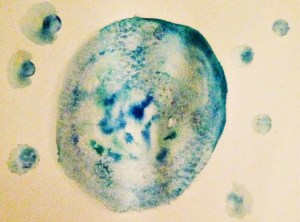

IMG_6591